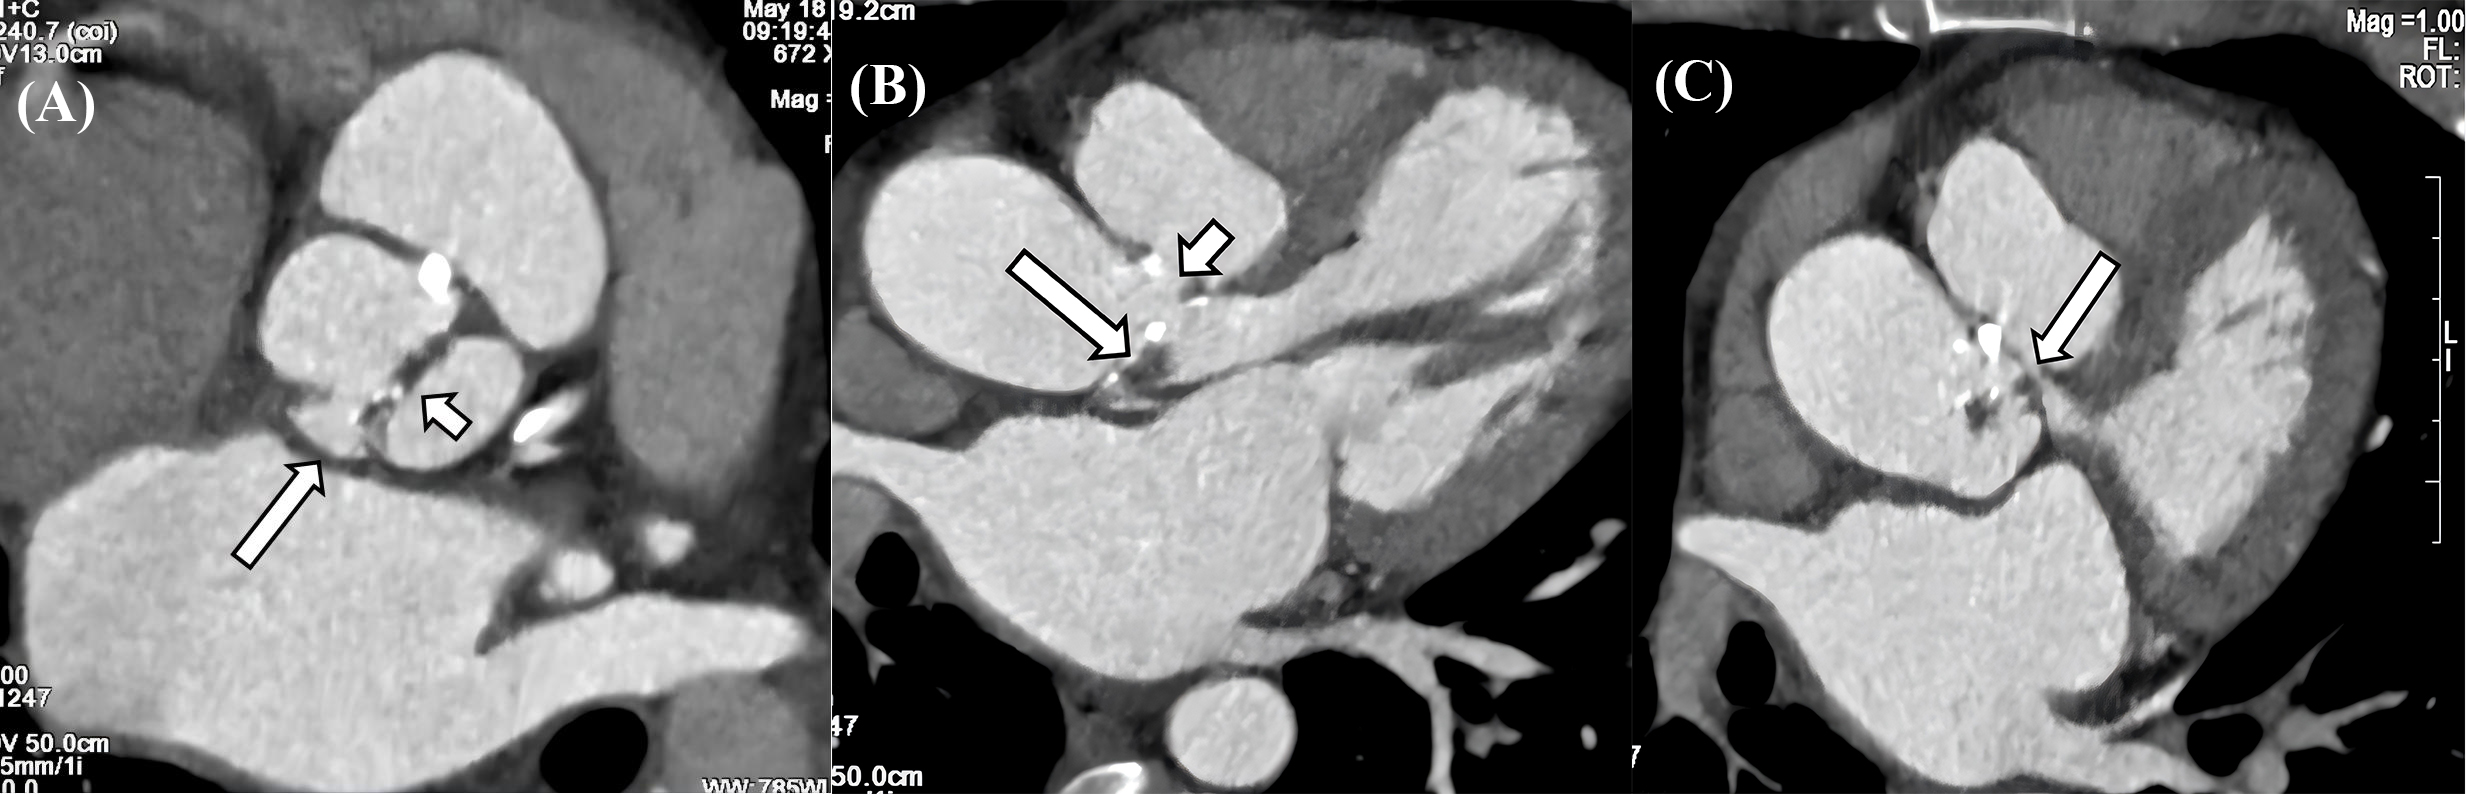

Fig. 3. CT characteristics of IE. (A) Valve thickening, calcification and penetrating ulcer in the aortic valve. The aortic sinus consists of two sinuses, and the aortic valve is a bicuspid valve. There is thickening and calcification of the valve leaflets (long arrow), and a penetrating ulcer is formed in the right coronary sinus (short arrow). (B) Vegetation, pseudoaneurysm, and leakage in aortic valve. The aortic valve leaflets show thickening with vegetations formation (long arrow), and a pseudoaneurysm is observed on the aortic valve, along with a large leakage between the aorta and the valve (short arrow). (C) Pseudoaneurysm with LVOT communication. A large pouch-like structure is present in the left anterior aspect of the aortic sinus, situated above the aortic valve, with small channels observed communicating with the LVOT (long arrow). CT, computed tomography; IE, infective endocarditis; LVOT, left ventricular outflow tract.